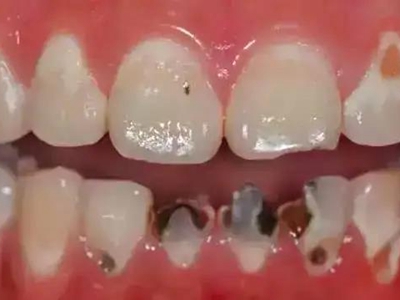

酸蚀症牙齿缺损颜色加深图

酸蚀症患者的牙齿牙冠面会出现多处缺损,下列牙齿均有不同大小的坑洞,表面坑洼不平,缺损处颜色加深,呈黄色至黑褐色,需进行牙齿修复治疗。